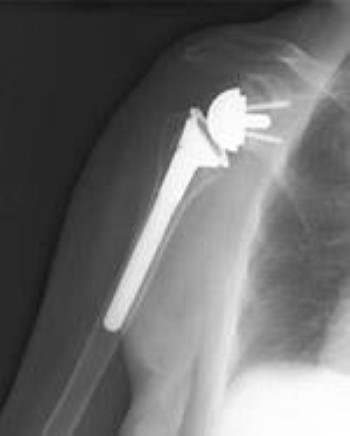

Reverse Total Shoulder Replacement

Another type of shoulder replacement is called reverse total shoulder replacement. Reverse total shoulder replacement is used for people who have:

- Completely torn rotator cuffs with severe arm weakness

- The effects of severe arthritis and rotator cuff tearing (cuff tear arthropathy)

- Had a previous shoulder replacement that failed

An x-ray of a reverse total shoulder replacement.

For these individuals, a conventional total shoulder replacement can still leave them with pain. They may also be unable to lift their arm up past a 90-degree angle. Not being able to lift one's arm away from the side can be severely debilitating.

In reverse total shoulder replacement, the socket and metal ball are switched. That means a metal ball is attached to the shoulder bone and a plastic socket is attached to the upper arm bone. This allows the patient to use the deltoid muscle instead of the torn rotator cuff to lift the arm.

(Left) Rotator cuff arthropathy. (Right) The reverse total shoulder replacement allows other muscles — such as the deltoid — to do the work of the damaged rotator cuff tendons.